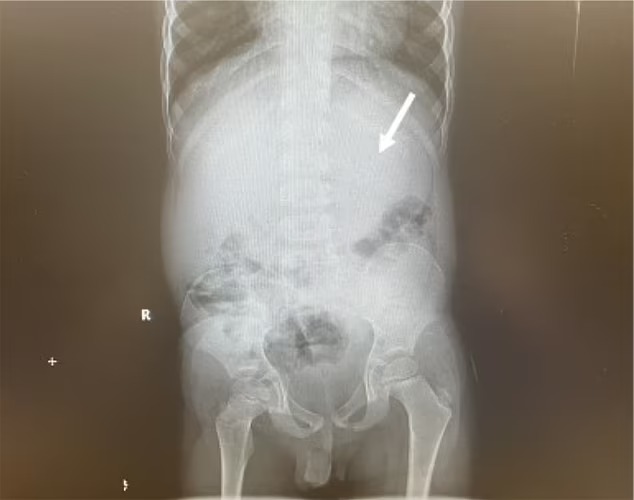

أما عن الطفل المريض، فكشفت الفحوصات فيما بعد أنه كان لديه كتلة كبيرة من مادة غريبة عالقة في معدته، وتشغل حوالي 25% من المساحة،، لذلك قرر الأطباء إزالته باستخدام ممرات متعددة للمريء، ثم يتم بعد ذلك وضع الأدوات الأخرى مثل الملقط أسفل الأنبوب، واستعماله لسحب أجزاء من الجسم المراد إزالته، وبالتالي يتم إحضارها مرة أخرى من خلال الحلق.